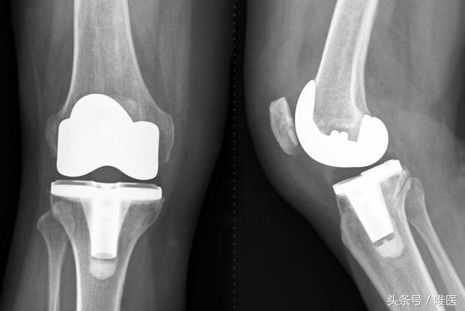

在临床中,总有一部分患者对于上述的保守治疗效果都不理想,这个时候,我们就需要通过手术来帮助他们解决问题。对于晚期的严重的膝关节骨关节炎而言,我们通常需要实行人工全膝关节置换术来帮助这些患者。人工全膝关节置换术是上个世纪出现的手术,也是现代骨科发展史上最为成功的手术之一,它能非常有效地根除晚期膝关节病痛,极大地提高病人的生活质量。目前,我国的人工全膝关节置换术开展已越来越普遍,成为了治疗晚期膝关节骨性关节炎的首选方法。

简单的说,这一手术就是将病变严重的膝关节股骨一侧和胫骨一侧的软骨和部分骨质以特殊的工具去除,然后根据每一个患者的膝关节尺寸选择合适型号的假体,用一种叫做骨水泥的粘合剂固定在膝关节内。通过这种手术,患者可以很快的正常行走和进行日常生活工作。